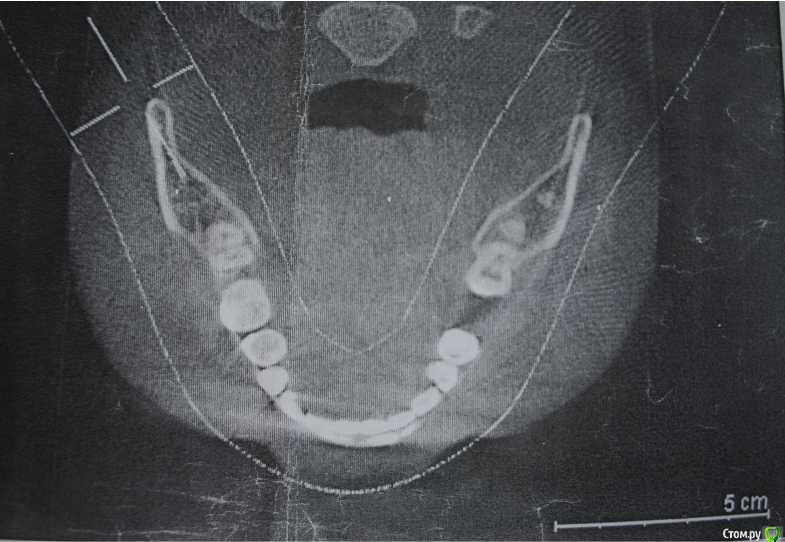

Лена35 Опубликовано 29 января, 2015 Поделиться Опубликовано 29 января, 2015 Уважаемые доктора, огромная просьба проконсультировать по поводу беспокоящей меня уже продолжительное время ситуации. С апреля 2013 года началось активное лечение зубов с эндодонтии на двух нижних передних зубах, пришлось и разрез сделать для удаления гноя. После этого сразу же появилось стойкое ощущение онемения губы и подбородка слева. Это ощущение есть до сих пор, иногда стало покидать, но возвращается, может по нескольку дней не быть. С тех пор было пролечено и депульпировано много зубов, потому что они стали болеть, но после всех депульпирований зубы продолжают также болеть по году. Нижние два передних болели 1,5 года и всетаки перестали болеть. Сейчас болят депульпированные верхние 5, 6 ,7 справа, нижняя 5 справа. Лечение было проведено качественно с микроскопом. После лечения в сентябре 2014 (4 месяца назад) 6 зуба справа был сделан в дешевой клинике 25летним доктором специальный укол для анестезии между челюстями, просили открывать рот до невозможности. После чего воспалился височно нижнечелюстной сустав справа, боли были острые в течение месяца. Было вправление вывиха. После чего маленькая дочка очень сильно ударила головой случайно в полуоткрытую челюсть слева и у меня распух внчс слева и появилась острая боль в суставе, режущая боль в ухе и боль жгучая в области выявившихся на томограмме инородных тел в области вырванного 10 лет назад зуба мудрости внизу слева. Все 10 лет меня этот зуб не беспокоил, изредка я ощущала небольшой дискомфорт там, как будто зуб растет и думала, что это фантомные боли. Они были кратковременные и не мешали мне жить. А вот с сентября боли в этом месте постоянные, изнуряющие. Я уже обошла нескольких многоуважаемых челюстно-лицевых хирургов в Новосибирске. 6 хирургов сообщили, что это либо остатки зуба, которые обызвествились, либо остеома, в обоих случаях беспокоить эти элементы не должны и в практике хирургов нет случаев острых болей из-за таких элементов. В это же время посетила профессора по внчс - диагноз - миофасцеальный болевой синдром и цементомы, которые не являются источником болей. Направлена на лечение к неврологу и ортопеду. На данном этапе прохожу пришлифовки суперконтактов, челюсть была не на месте из-за неправильного прикуса перекрестного, который случился из-за множественных пломб, не подогнанных под прикус - воспаление суставов могло из-за этого начаться. Далее диагноз - умеренный деформирующий артроз суставов. Прохожу лечение у невролога - просто принимаю препараты - пиакследин, артра, катадолон, курсами нвпс, мажу диклофенак, хондра. Во вторник установлю аква сплинт – для снятия мышечного напряжения, улучшения работы нейро-мышечного аппарата и снятия болевого синдрома. Все что меня беспокоит – это боль. Также пришлифовки у ортопеда и в перспективе фиксация прикуса коронками на жевательных зубах и поднятие прикуса. Забыла отметить, что 7 доктор по КТ сделал вывод, что инородные тела находятся в зоне нижнелуночкового нерва, могут вызывать компрессию и подлежат удалению. Но остальные 6 хирургов – кандидатов и докторов наук – выражают опасения, что при удалении нужно будет вырезать большой кусок челюсти, могут быть травмированы значительное количество нервных пучков и сам нижнелуночковый нерв и тройничный нерв и тогда мне станет намного хуже. Я очень боюсь такой операции, но постоянная боль в этой зоне изводит меня. Последний хирург сказал, что рядышком травмированы связки при вывихе, и это они дают туда эту боль. Десна в этом месте нормальная, гладкая, розовая, иногда в десне дискомфорт при жевании, но с этим можно жить. Боль в области элементов такая: жгучая, режущая, после катадолона или нвпс становится тупой. Важно – ночью – ничего не болит! Ни зубы, ни элементы, ни суставы! Как только начинаю говорить или двигать шеей – начинается боль, к обеду она сильная, к вечеру еще хуже. Нейростоматолог считает, что от множественных стоматологических вмешательств и длительного открывания рта произрастает боль и что в мозгу у меня уже сформировалась зацикленность и болевая доминанта, советует амитриптилин и ничего не удалять. Ведь пока я не знала об этих элементах – то и не болело там. А как узнала – сразу боль. Пью противотревожные - Стрезам, фенибут, персен. Как стала их пить – стало полегче – перестало пугать подергивание по линии тройничынх ветвей слева и отношение к проблеме стало более ровное. Конечно мое состояние тревоги и страха накопилось уже в нереальной степени, ведь я почти два года испытываю боли, сначала зубные, потом суставные и вот эти – в области элементов, которые меня страшно пугают из-за возможной операции, которая грозит невритом, параличом. Но испытывать такую боль всю оставшуюся жизнь я тоже не смогу. Очень важно ваше мнение – что мне делать – ждать, удалять эти элементы или думать, что боль идет от суставов и спазмированных мышц и лечить суставы. Мне очень морально тяжело, не сойти бы с ума. Может и правда пропить антидепрессанты. Но от них же не пройдет боль. Заранее благодарна за помощь. Прилагаю компьютерную томограмму. Ссылка на комментарий

Korel Опубликовано 29 января, 2015 Поделиться Опубликовано 29 января, 2015 С удалением остатка 38 никаких проблем не будет. Что касается образования, расположенного на уровне нижнечелюстного канала, нужны доп. исследования. Снимок не очень хорошего качества. Ссылка на комментарий

Alejandro Опубликовано 29 января, 2015 Поделиться Опубликовано 29 января, 2015 Соглашусь с коллегой: корень восьмёрки не проблемный, а вот что там у вас в области самого канала? Нужны более чёткие снимки... Ссылка на комментарий

Лена35 Опубликовано 30 января, 2015 Автор Поделиться Опубликовано 30 января, 2015 С удалением остатка 38 никаких проблем не будет. Что касается образования, расположенного на уровне нижнечелюстного канала, нужны доп. исследования. Снимок не очень хорошего качества.У меня несколько компьютерных томограмм в динамике. На всех это инородное тело выглядит именно так. Мнения разделились - или обызвествленные остатки зуба, либо остеомы, но они не растут. Лично я вижу, что это корень у десны и часть зуба у луночкового нерва. Что будет, если при удалении низко расположенного образования будет поврежден или перерезан нижнелуночковый нерв? Ссылка на комментарий

Korel Опубликовано 30 января, 2015 Поделиться Опубликовано 30 января, 2015 (изменено) У меня несколько компьютерных томограмм в динамике. Покажите их, если не трудно. Стоит ли удалить корень и посмотреть не пройдут ли онемение губ и подбородка, а нижний элемент оставить? Для начала нужно определиться с образованием ниже, а корень возможно удалить "по пути". Он один вряд ли будет давать такую клинику. Есть вероятность, что образование ниже также фрагмент 38, тогда особых проблем быть не должно. Изменено 30 января, 2015 пользователем Korel Ссылка на комментарий

Alejandro Опубликовано 31 января, 2015 Поделиться Опубликовано 31 января, 2015 Сделайте скриншоты из вашей 3д программы и залейте их в тему через радикал, вторая ссылка. Причём нужны скриншоты именно образования в области нижнечелюстного канала. Ссылка на комментарий